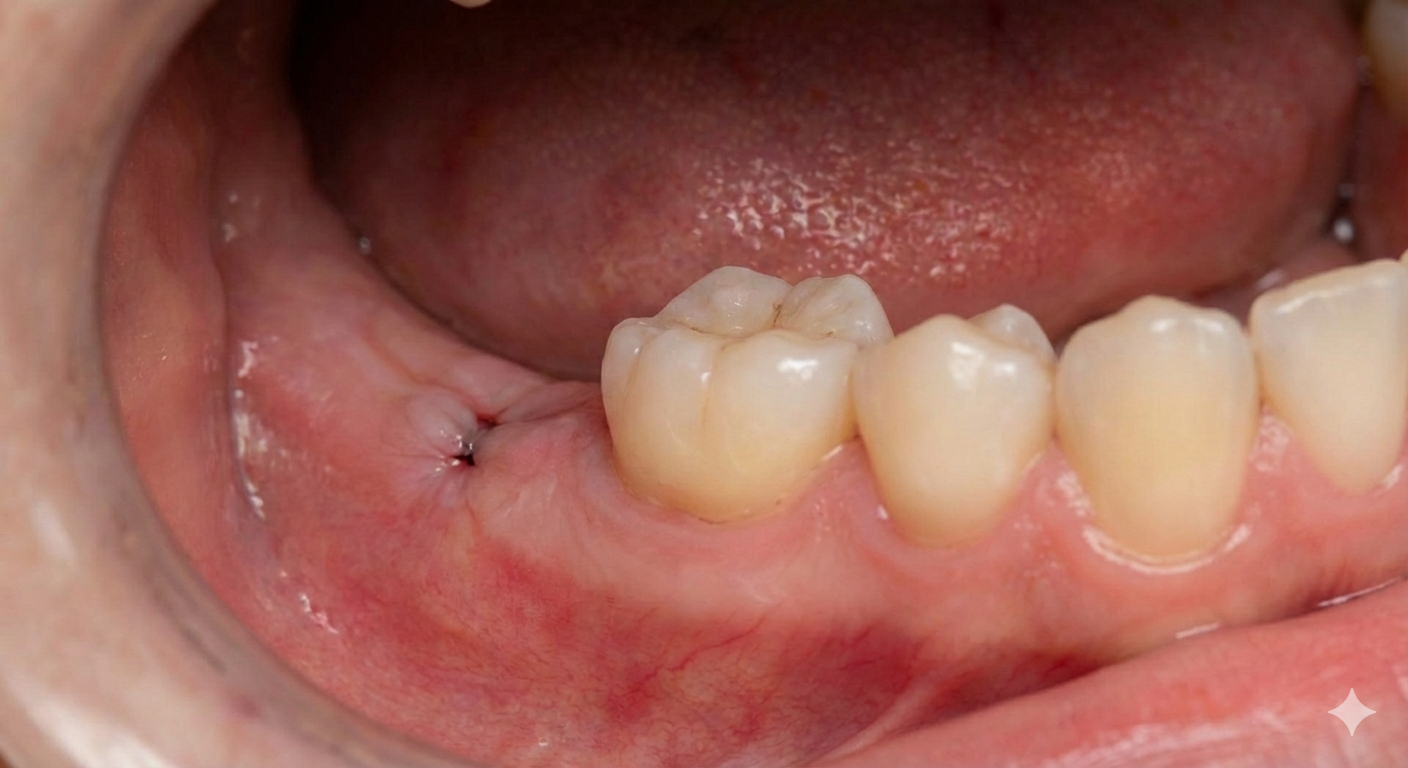

Certain dental issues require surgical intervention, and minor oral surgery provides targeted relief for a healthier, pain-free mouth.